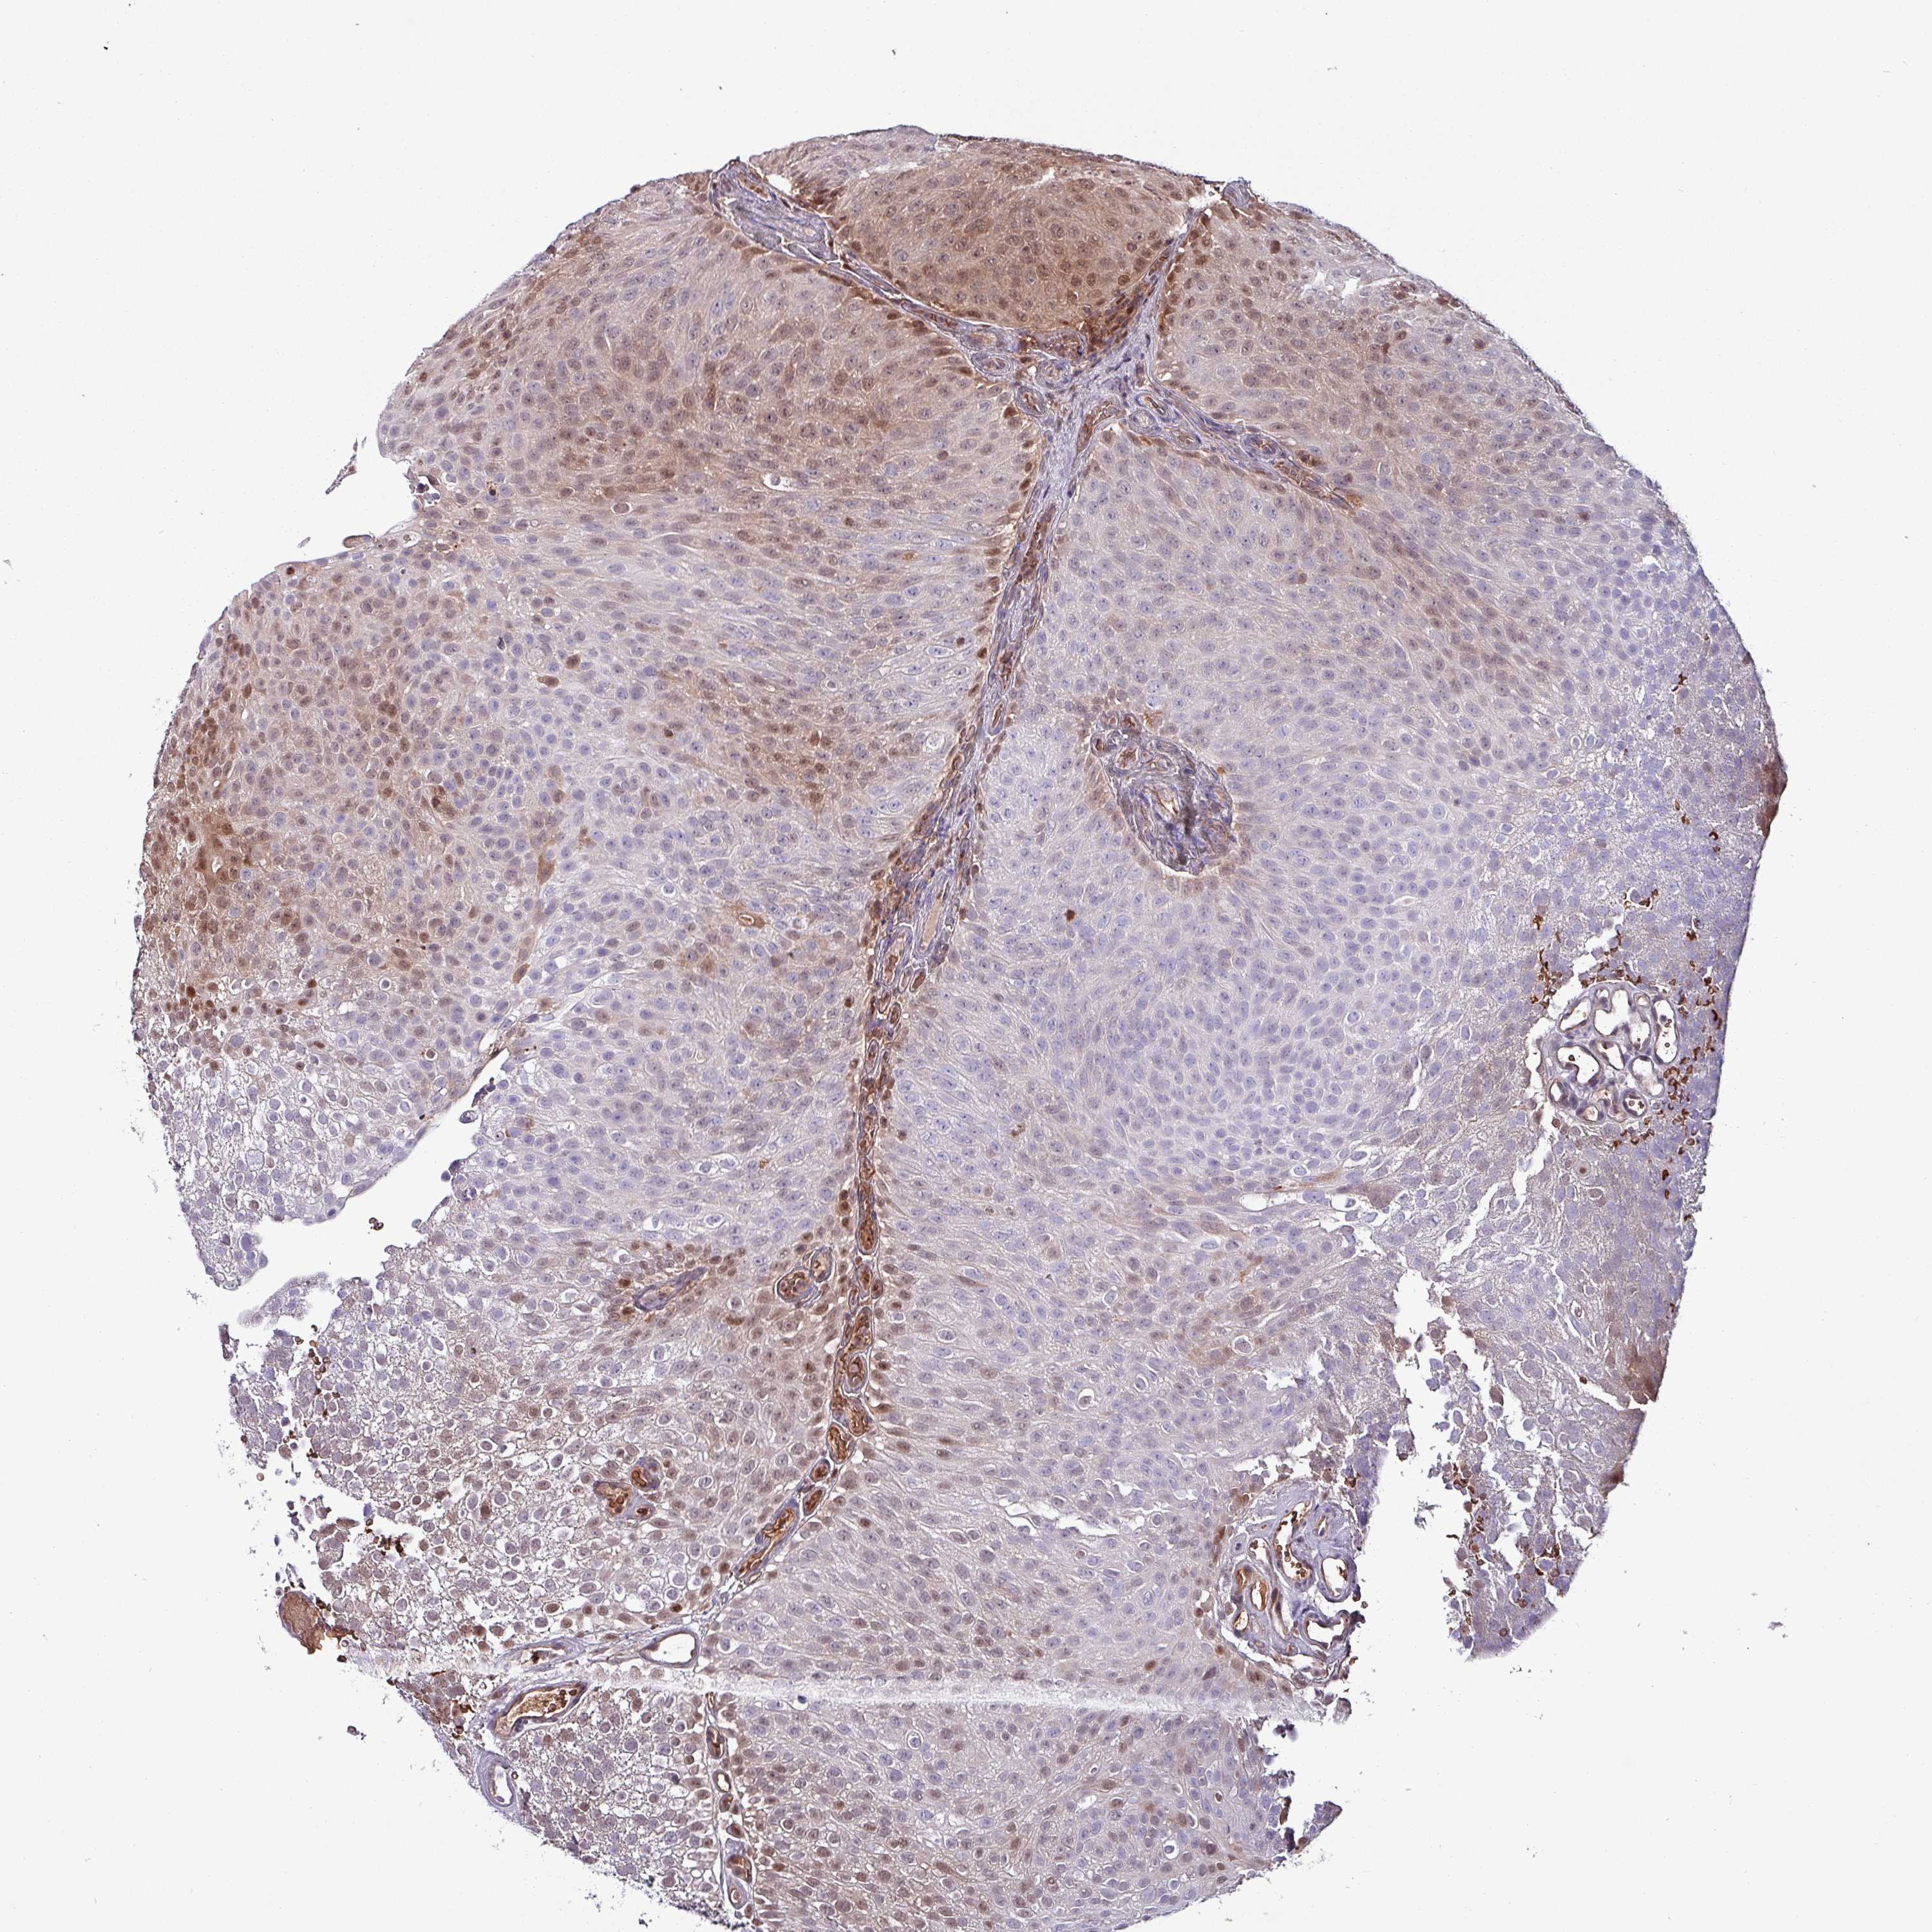

UROTHELIAL CANCER - Protein expressioni

A mouse-over function shows sample information and annotation data. Click on an image to view it in a full screen mode. Samples can be filtered based on level of antibody staining by selecting one or several of the following categories: high, medium, low and not detected. The assay and annotation is described here.

Antibody stainingi

Antibody staining in the annotated cell types in the current human tissue is reported as not detected, low, medium, or high, based on conventional immunohistochemistry profiling in selected tissues. This score is based on the combination of the staining intensity and fraction of stained cells.

Each image is clickable and will lead to virtual microscopy that enables deeper exploration of all samples and also displays staining intensity scores, fraction scores and subcellular localization as well as patient and tissue information for each sample.

Antibody HPA046995

Antibody HPA050327

Urothelial carcinoma, High grade

Urothelial carcinoma, Low grade

Urothelial carcinoma, NOS